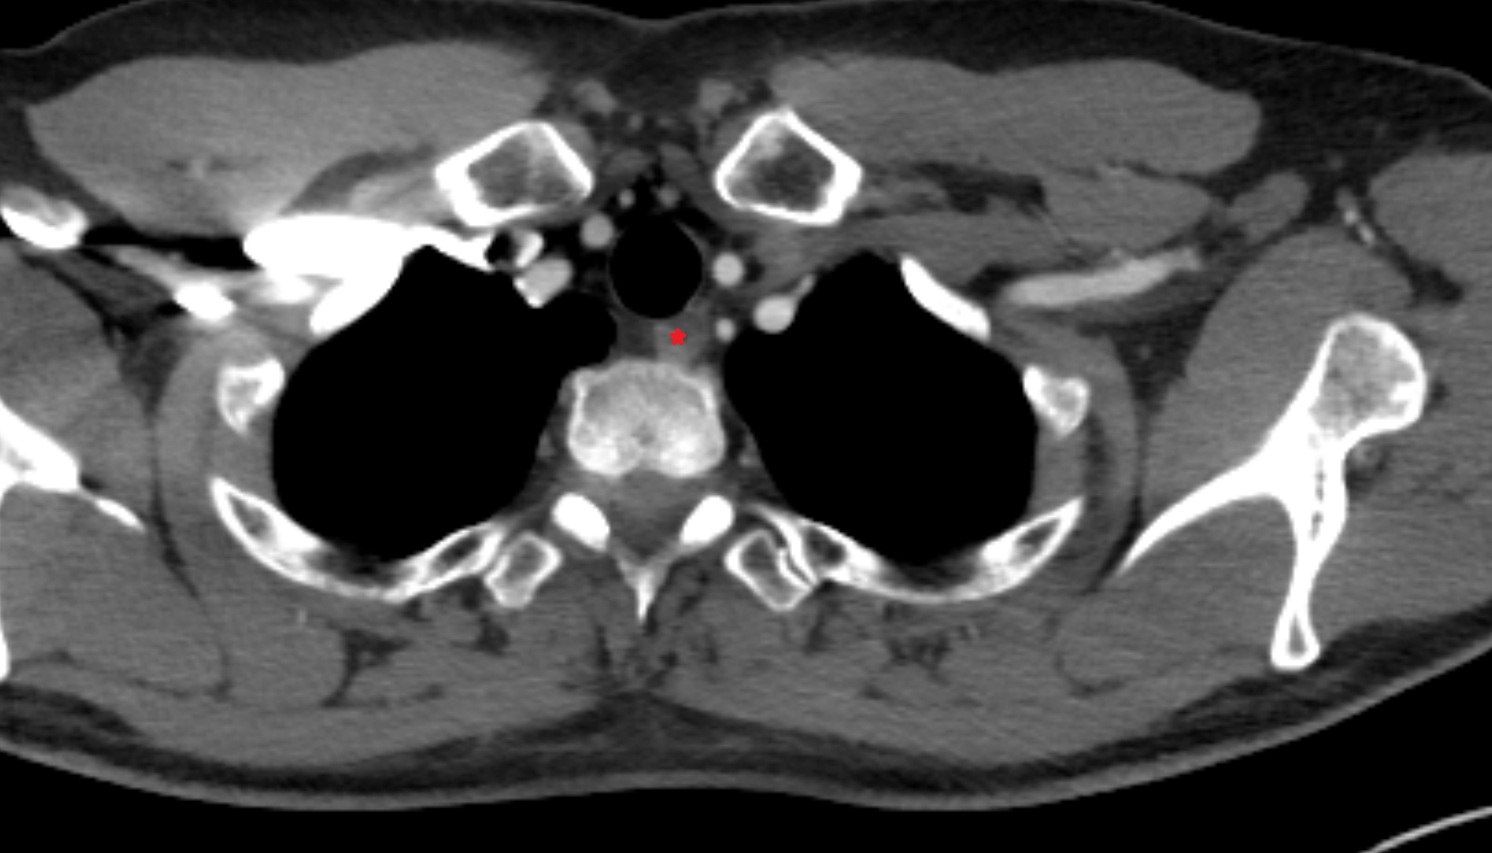

- Trachea

- Common carotid artery

- Internal carotid artery (cervical part)

- Subclavian artery

- Clavicle